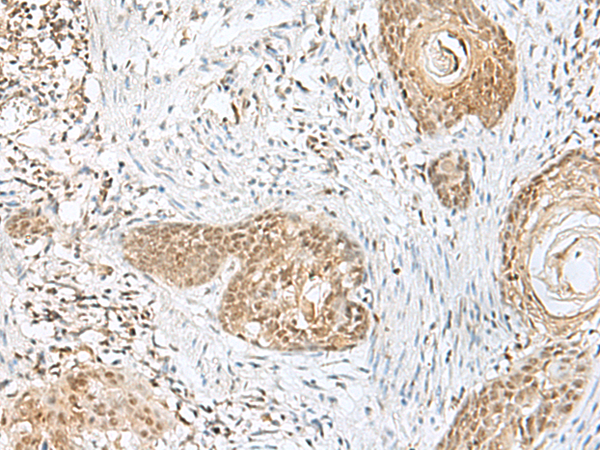

分类: 科研抗体货号: P10627别名: ndrp; BRWD2; DIDOD; WDR11; DCAF14; CHUJANS应用: IHC反应种属: Human, Mouse